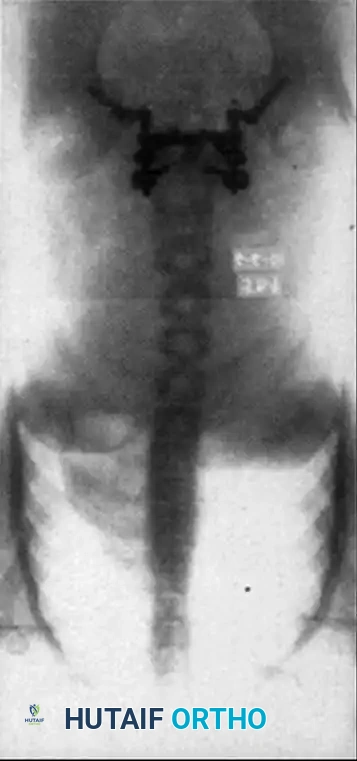

- Standing Lateral View: Mandatory for assessing the true degree of slippage. Lowe et al. demonstrated a 26% increase in measured slip on standing films compared to supine films.

- Anteroposterior (AP) View: Evaluates for concurrent scoliosis and transverse process anatomy.

Comprehensive preoperative planning requires full-length standing scoliosis films to calculate pelvic parameters (Pelvic Incidence, Pelvic Tilt, Sacral Slope).